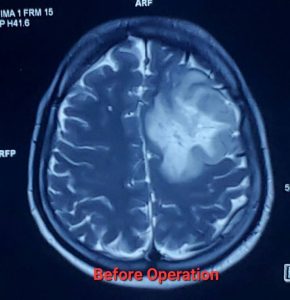

লো-গ্রেড গ্লিওমা (Low-Grade Glioma - LGG)

লো-গ্রেড গ্লিওমা (Low-Grade Glioma – LGG) হলো মস্তিষ্কের টিউমার যা মস্তিষ্কের সহায়ক কোষ (গ্লিয়াল সেল) থেকে তৈরি হয়। এগুলি সাধারণত ধীর গতিতে বৃদ্ধি পায়, তবে সময়ের সাথে সাথে এগুলি আরও আগ্রাসী (উচ্চ-গ্রেডের) হতে পারে। সার্জারি লো-গ্রেড গ্লিওমার চিকিৎসার একটি গুরুত্বপূর্ণ অংশ।

* সর্বাধিক সম্ভব টিউমার অপসারণ (Maximal Safe Resection): নিউরোসার্জনরা যতটা সম্ভব টিউমারের অংশ অপসারণ করার চেষ্টা করেন, যাতে মস্তিষ্কের গুরুত্বপূর্ণ কার্যকারিতার (যেমন – কথা বলা, নড়াচড়া, স্মৃতিশক্তি) ক্ষতি না হয়। কিছু ক্ষেত্রে, সম্পূর্ণ টিউমার অপসারণ সম্ভব না হলেও, আংশিক অপসারণও রোগের অগ্রগতি ধীর করতে এবং লক্ষণগুলি কমাতে সাহায্য করতে পারে।

লো-গ্রেড গ্লিওমা সার্জারির পর prognosis বেশ ভালো হতে পারে, বিশেষ করে যদি টিউমার সম্পূর্ণ বা বেশিরভাগ অংশ অপসারণ করা যায়। গবেষণায় দেখা গেছে, দ্রুত এবং কার্যকরী সার্জারি জীবনকাল বাড়াতে এবং খিঁচুনি নিয়ন্ত্রণে আনতে সাহায্য করে। যদিও লো-গ্রেড গ্লিওমা সাধারণত ধীর গতিতে বৃদ্ধি পায়, তবুও এটি সময়ের সাথে সাথে উচ্চ-গ্রেডে পরিবর্তিত হতে পারে। তাই নিয়মিত ফলো-আপ এবং প্রয়োজনে অন্যান্য চিকিৎসা,যেমন – রেডিয়েশন থেরাপি বা কেমোথেরাপি, অত্যন্ত গুরুত্বপূর্ণ।